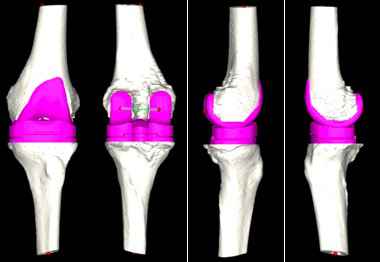

对此,张弛团队在与患者及家属充分沟通后,决定使用人工智能系统辅助置换全膝关节。专家在系统中上传患者的CT资料,人工智能便快速完成了术前规划,其模拟的假体型号及角度、位置十分精准。

人工智能术前规划模拟出精准的假体大小和位置。

“传统的全膝关节置换术极其依赖术中所见及骨科医生的临床经验,医生常需于术中反复比对以寻找最适假体大小,由于患者个体差异大、病情复杂等问题,导致全膝关节置换术后患者满意度偏低。”张弛解释说,“该患者病情复杂,通过人工智能辅助,能够在术前精准规划,帮助手术更快速、更精准的实现。”